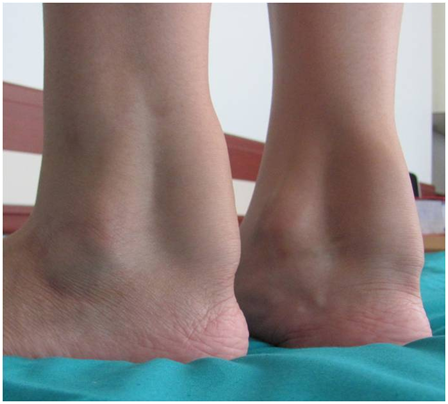

19-year-old woman presented with pain and swelling at back of the ankle joint over one month (Figure 1). She reported diffuculty in walking. She had no history of injury, trauma or infection. She had sickle cell anemia trait and bilateral cataract surgery at eight years old. On physical examination, there were firm and fixed swelling with an average diameter between 2 and 3 cms, bilaterally on the posterior aspect of the ankle. Bilateral Achilles tendons were tender. Other general and systemic examinations were normal.

Figure 1 Bilaterally swelling on the posterior aspect of the ankle.